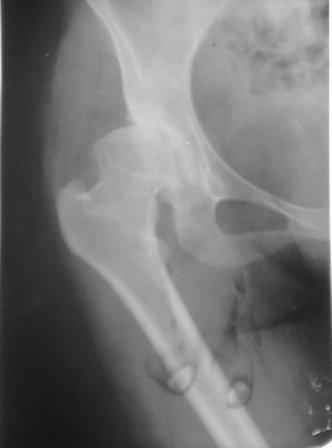

Типичная концовка проигнорированного диспластического состояния сустава. Дисплазия тазобедренного сустава часто встречающаяся патология у жителей Центральной Азии вследствие тугого пеленания в детстве. Традиционно ребенок находится в течение дня в так называемой кроватке "бешик", удобной в быту, но она впоследствии приводит к недоразвитию тазобедренного сустава.

Это первые признаки начала деструкции сустава, и возможно, аналгетики помогут для купирования болей, но в течение очень короткого времени от сустава ничего не останется, и в дальнейшем останется только артропластика.

При более сохранном суставе от дальнейшего разрушения можно было бы сохранить только периориентацией нагрузки на сустав - Периацетабулярной Остеотомией .

Данный сустав в начальной стадии разрушения, но все-таки я бы сделал обзорный таз и отдельные снимки сустава в 30 градусной абдукции и аддукции. Также снимки с внутренней и наружной ротацией для оценки состояния головки бедра.